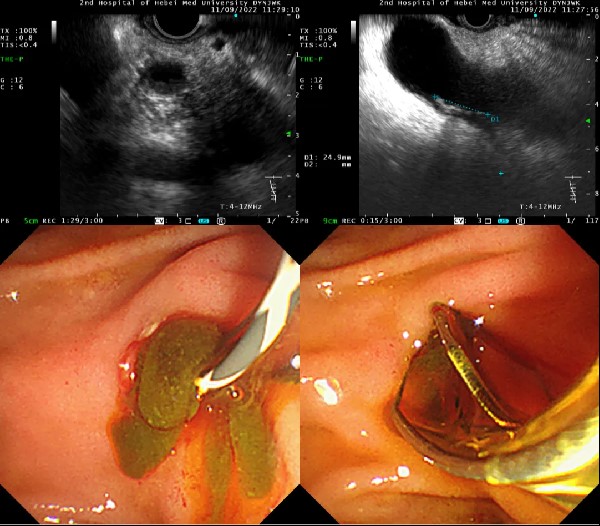

患者首先行超声内镜检查术,超声内镜发现胆总管壁增厚,内泥沙样结石明确,这更加验证了团队的术前诊断。遂由张立超副主任医师行无X线ERCP,因患者手术体位不理想,对手术操作造成了极大的困难,通过多次、反复的术中调整,终插管成功并抽出大量脓性胆汁,应用取石网篮将大量泥沙样结石取出,随后置入鼻胆管引流。解除胆道梗阻后数日,患者各项指标趋于好转,拟于近期转回普通病房。